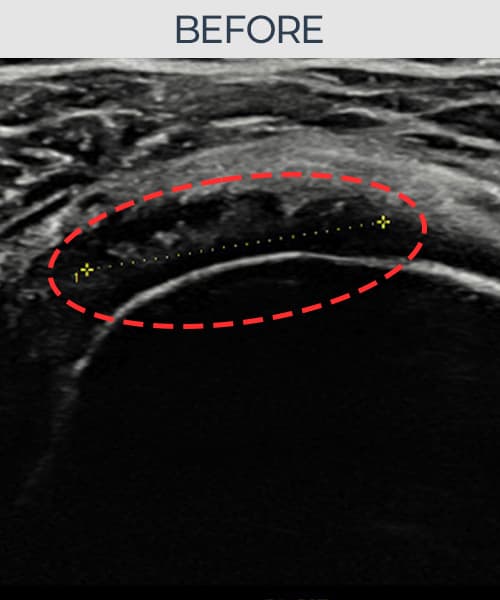

[촬영시기:23.09.01~23.11.03]

[어깨인대 축소봉합술] 우측 어깨 통증이 수개월간 지속되어 내원하셨습니다.